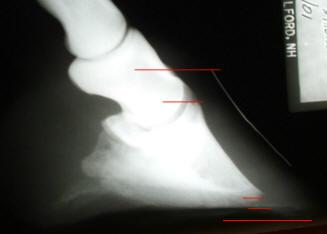

Fig. 2) Feral cadaver with healthy

hoof wall/P3 relationship. The lateral cartilages, the laminae and coronary

papillae have been left intact in the photo. Again, we see a very short hoof

capsule (3 1/2 inch toe in a #2 sized foot), coupled with tremendous sole

thickness made possible because of the correct bone/wall relationship.